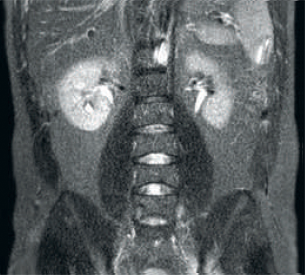

ingenia image